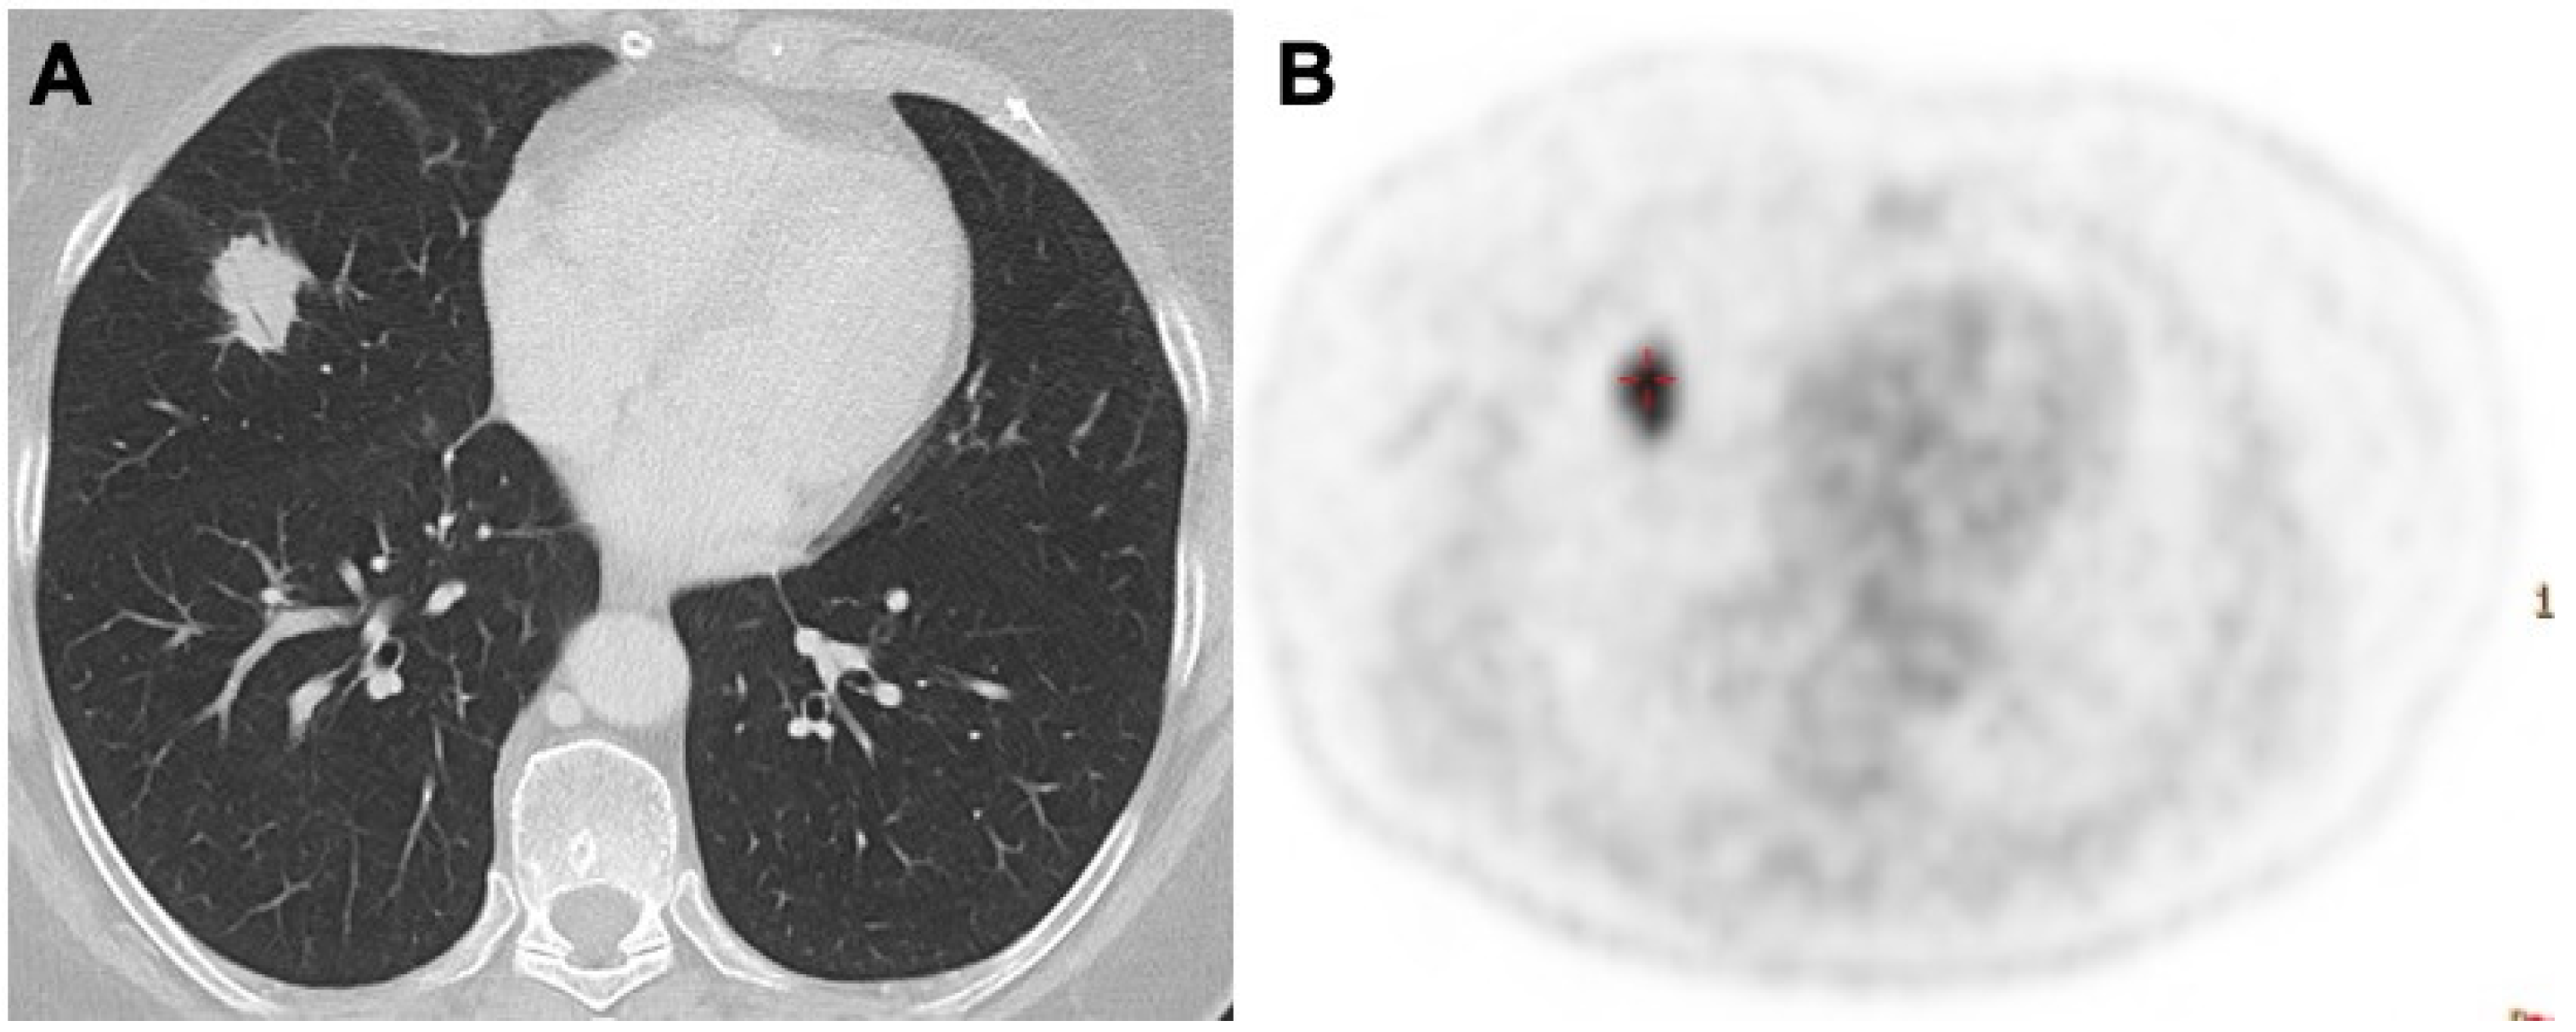

3.2. Nodules and Masses

- Juweid, M.E.; Stroobants, S.; Hoekstra, O.S.; Mottaghy, F.M.; Dietlein, M.; Guermazi, A.; Wiseman, G.A.; Kostakoglu, L.; Scheidhauer, K.; Buck, A.; et al. Imaging Subcommittee of International Harmonization Project in Lymphoma. Use of positron emission tomography for response assessment of lymphoma: Consensus of the Imaging Subcommittee of International Harmonization Project in Lymphoma. J. Clin. Oncol. 2007, 25, 571–578. [Google Scholar] [CrossRef] [PubMed]

- Enomoto, K.; Hamada, K.; Inohara, H.; Higuchi, I.; Tomita, Y.; Kubo, T.; Hatazawa, J. Mucosa-associated lymphoid tissue lymphoma studied with FDG-PET: A comparison with CT and endoscopic findings. Ann. Nucl. Med. 2008, 22, 261–267. [Google Scholar] [CrossRef] [PubMed]

- Albano, D.; Borghesi, A.; Bosio, G.; Bertoli, M.; Maroldi, R.; Giubbini, R.; Bertagna, F. Pulmonary mucosa-associated lymphoid tissue lymphoma: F-FDG PET/CT and CT findings in 28 patients. Br. J. Radiol. 2017, 90, 20170311. [Google Scholar] [CrossRef]

- Cozzi, D.; Dini, C.; Mungai, F.; Puccini, B.; Rigacci, L.; Miele, V. Primary pulmonary lymphoma: Imaging findings in 30 cases. Radiol. Med. 2019, 124, 1262–1269. [Google Scholar] [CrossRef]

- Bligh, M.P.; Borgaonkar, J.N.; Burrell, S.C.; MacDonald, D.A.; Manos, D. Spectrum of CT findings in thoracic extranodal non-Hodgkin lymphoma. Radiographics 2017, 37, 439–461. [Google Scholar] [CrossRef]